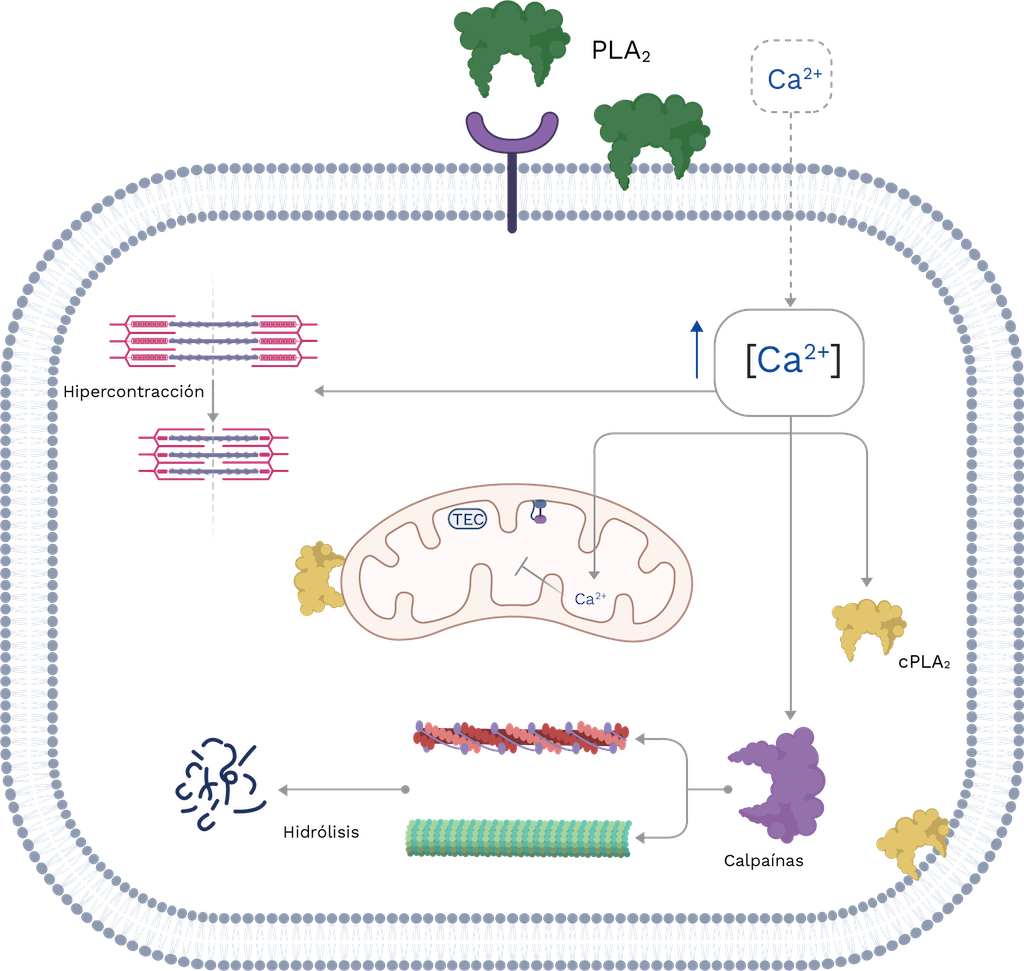

La concentración elevada de iones de calcio en el citoplasma de las células musculares conduce a una hipercontracción del sarcómero, lo que resulta en daño mecánico. Los iones de calcio también inducen una sobrecarga de las mitocondrias, lo que lleva a un daño en la cadena transportadora de electrones y la síntesis de ATP. Además, el calcio puede activar las PLA2 citosólicas que pueden aumentar el daño intracelular, particularmente en organelos con membrana; y también puede estimular la acción proteolítica de las calpaínas, desencadenando la desorganización del citoesqueleto. Finalmente, las PLA2 del veneno de serpiente pueden internalizarse, lo que lleva a un mayor daño interno. Estos eventos finalmente resultan en la muerte celular por necrosis (Figura 8), que es un factor significativo en el envenenamiento por vipéridos, incluidos los de Colombia (ver Capítulo 9) [111,112].

Figura 9. Representación esquemática de los eventos celulares que ocurren durante la miotoxicidad inducida por las PLA2 del veneno de serpiente. TEC: cadena transportadora de electrones; cPLA2: PLA2 citosólica. La membrana de la célula muscular se ve alterada por mecanismos catalíticos o no catalíticos de las PLA2, lo que conduce a una entrada masiva de Ca2+. Esto da como resultado una hipercontracción del sarcómero, la activación de la calpaína y la cPLA2, todo lo cual contribuye a aumentar el daño. Para más detalles, consulte el texto. Imagen creada con Bio Render y editada por Oscar A Ramírez Ruiz.